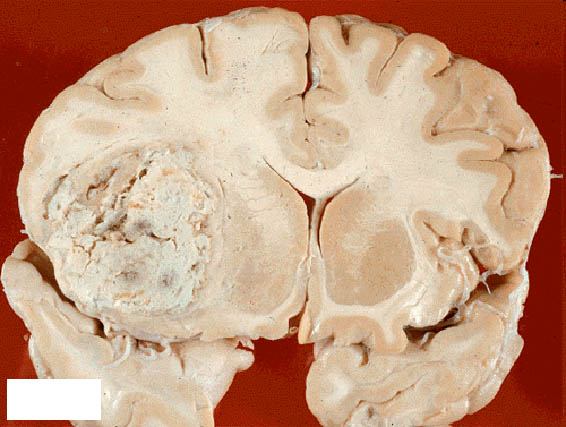

Злокачественные опухоли мозга, как правило, представляют собой метастазы злокачественных новообразований, развивающихся в другой части тела. Рак молочной железы и легких, злокачественная меланома и злокачественные заболевания крови, например лейкоз и лимфома, способны распространяться по кровеносному руслу и проникать в головной мозг. Метастазы могут возникать в одной или нескольких областях головного мозга. Первичные опухоли мозга растут из клеток самого головного мозга. Обычно это глиомы, образующиеся из глиальных клеток, которые окружают и поддерживают нейроны. Некоторые глиомы являются злокачественными, например наиболее распространенная из них мультиформная глиобластома. К другим злокачественным глиомам относятся быстро растущие анапластические астроцитомы, медленнее растущие астроцитомы и олигодендроглиомы. Довольно редкие медуллобластомы отмечаются у детей в период, предшествующий половому созреванию. Саркомы и аденокарциномы, образующиеся не из нервной ткани, встречаются нечасто. Опухоли мозга возникают с равной частотой независимо от половой принадлежности, но некоторые их виды более распространены у мужчин, а другие - у женщин. По неизвестным причинам в последнее время стали чаще появляться лимфомы головного мозга, особенно у больных СПИДом. Несмотря на лечение, только около 25% людей со злокачественными опухолями мозга живут больше двух лет. При определенных типах опухолей перспектива немного лучше, например при астроцитомах и олигодендроглиомах опухоль обычно не возобновляет своего роста в течение 3-5 лет после лечения. Около 50% людей, лечившихся по поводу медуллобластомы, живут более 5 лет после установления диагноза. Лечение злокачественной опухоли мозга имеет лучшие перспективы при анапластической астроцитоме, чем при мультиформной глиобластоме, а также если возраст больного не превышает 45 лет и если большая часть опухоли или вся она может быть удалена хирургически.